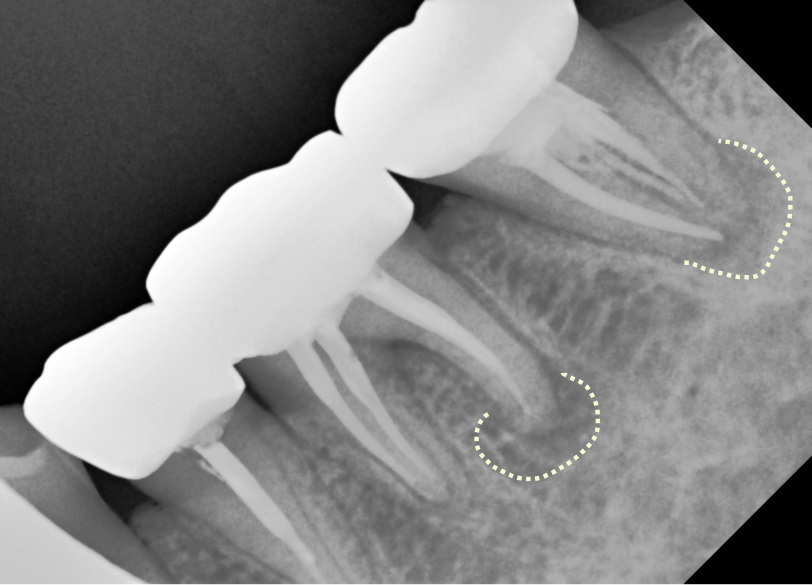

2. 신경관 충전이 불충분했던 경우

신경치료의 핵심은 **“완벽한 밀봉”**입니다.

단순히 공간을 채우는 게 아니라

뿌리 끝까지 밀봉해 세균 침투를 막아야 합니다.

✅ 충전이 뿌리 끝까지 도달하지 못한 경우

➡️ 충전 길이가 짧거나, 밀봉이 제대로 되지 않으면

➡️ 세균이 다시 번식하며 염증 유발

엑스레이 상에서 확인되는 충전 길이가

치근의 절반에도 못 미치는 경우라면

재신경치료가 꼭 필요합니다.

이 경우 역시 재처치만 잘 이루어진다면

자연치아를 보존할 가능성이 매우 높습니다.